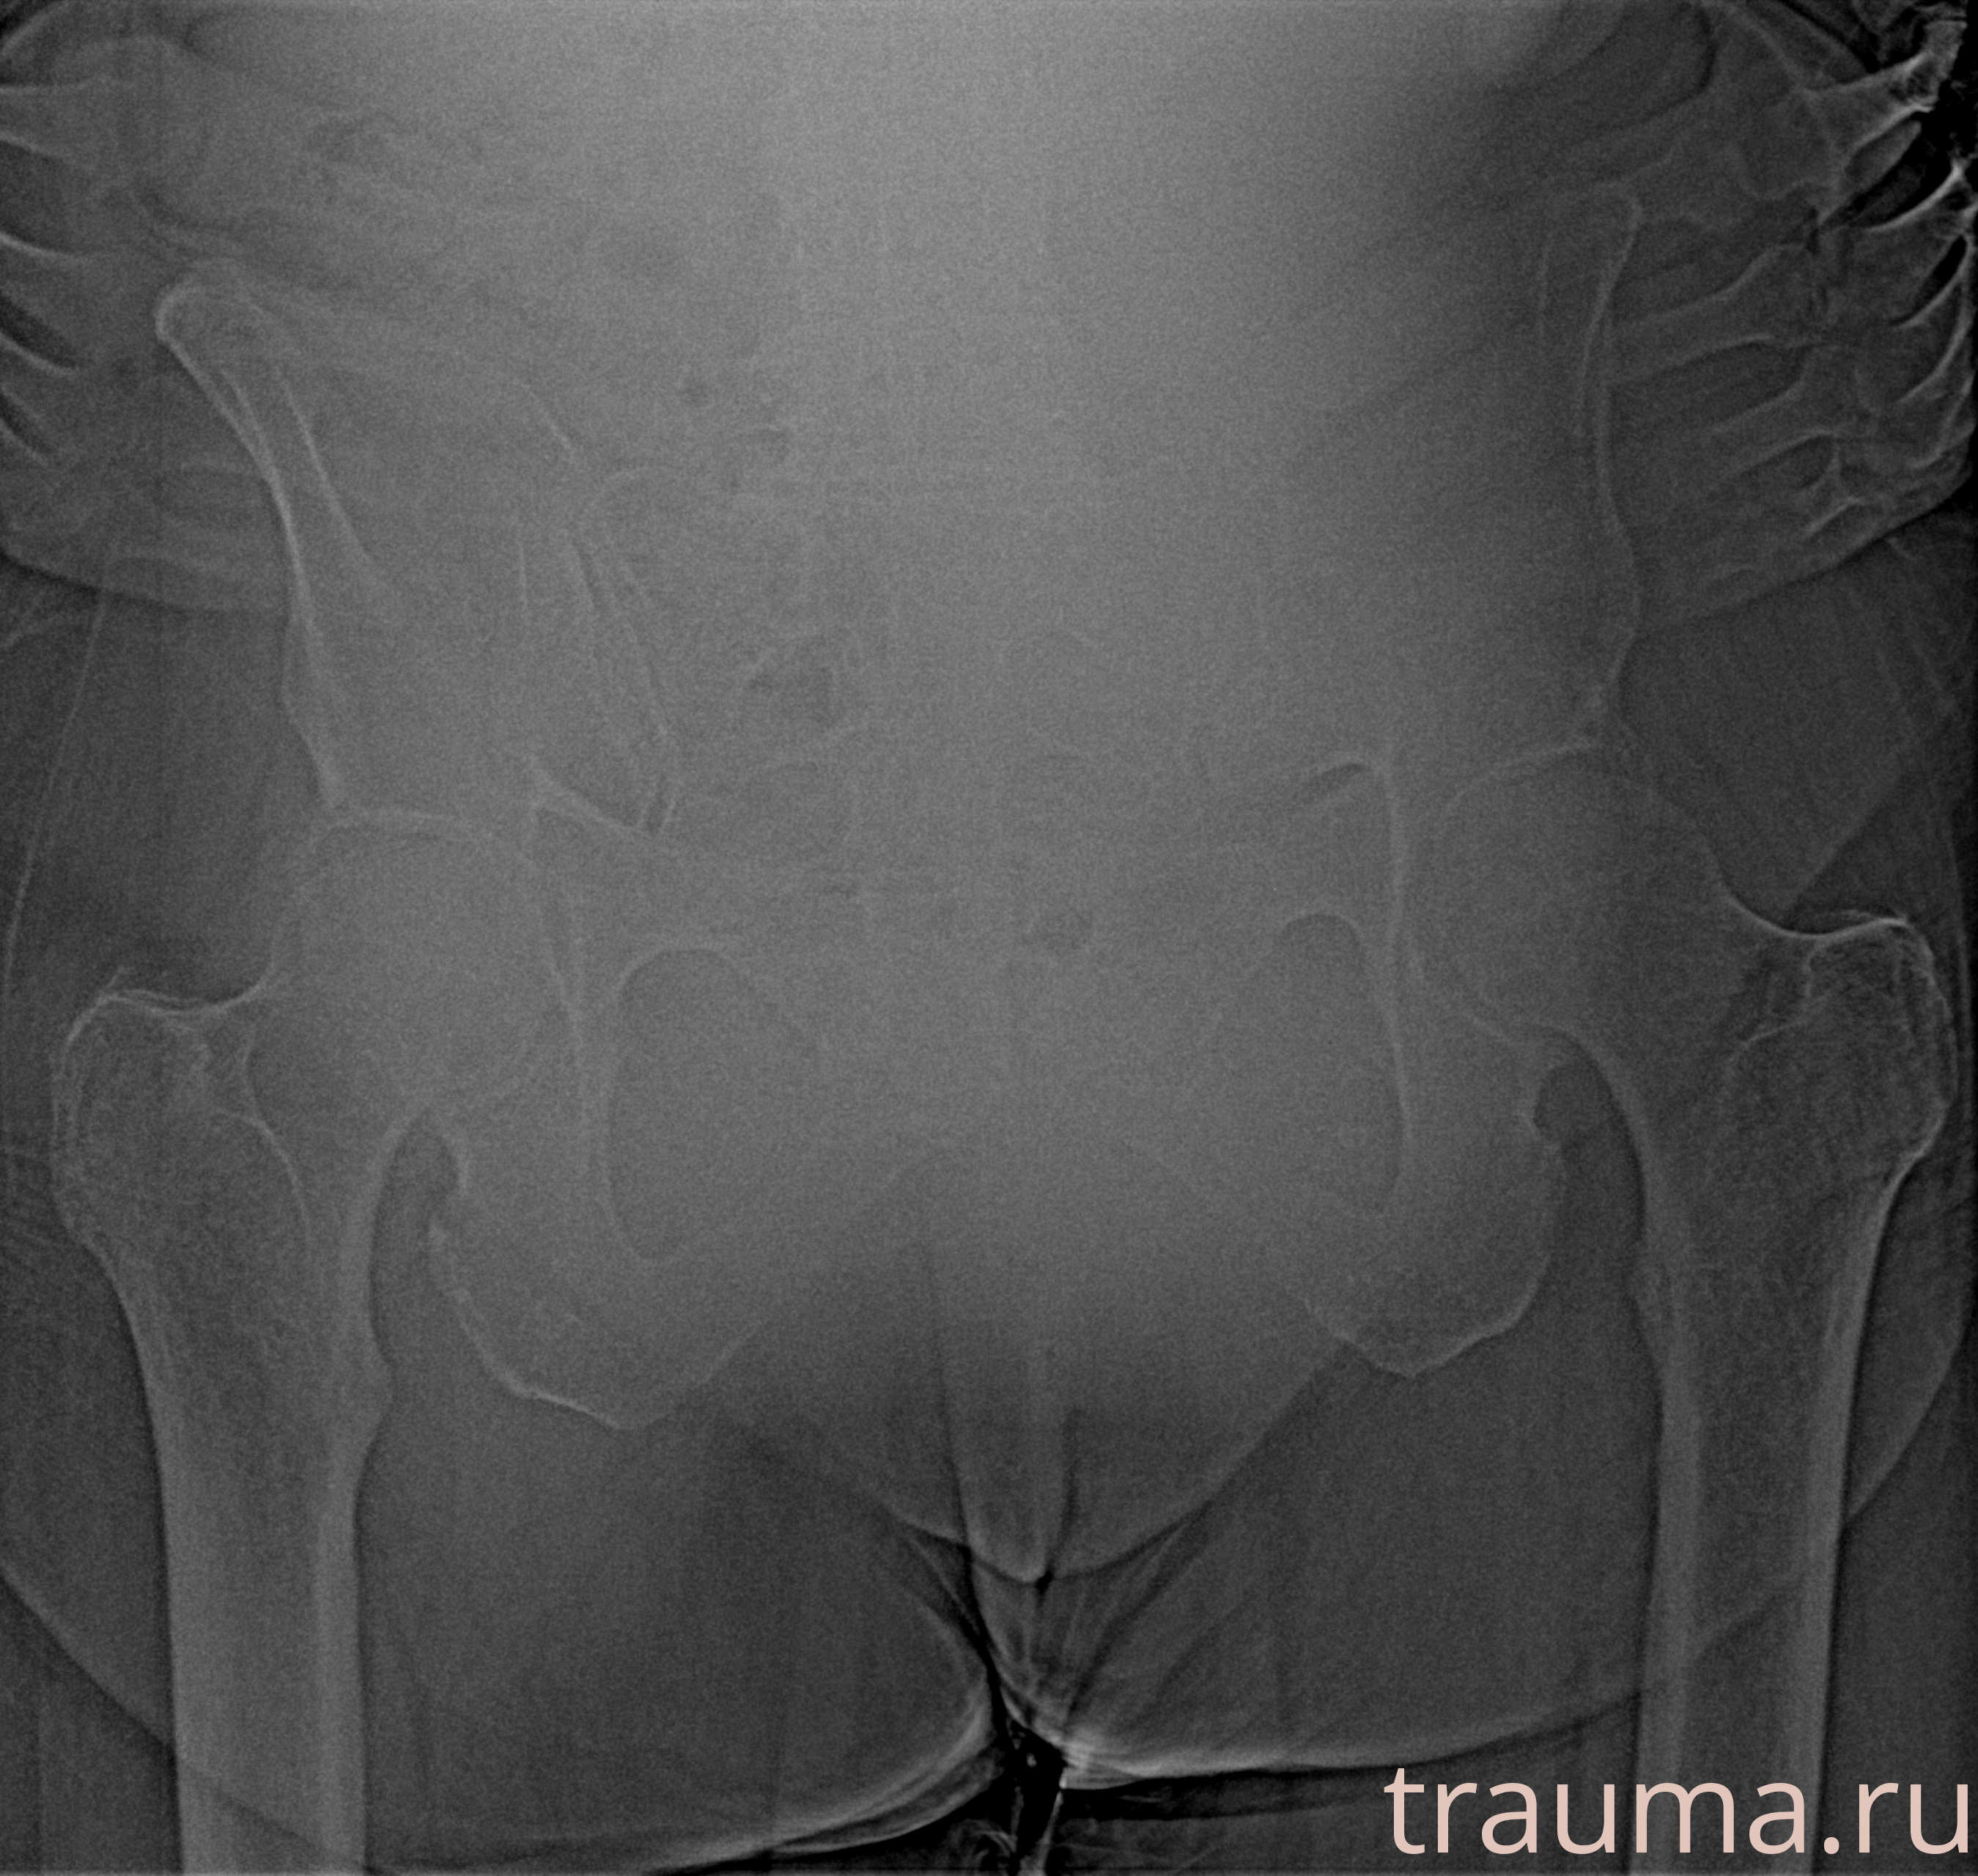

Рентген на дому: по вашему адресу приезжает врач-рентгенолог, травматолог-ортопед с мобильным рентгеновским аппаратом, проводит диагностику травмы или заболевания, делает необходимые рентгенограммы, дает рекомендации по дальнейшему лечению. Получить качественные снимки в домашних условиях возможно благодаря уникальной методике, разработанной МосРентген Центром для института  Склифосовского

при переломе шейки бедра и пневмонии от компании МосРентген Центр - партнера Института имени Склифосовского